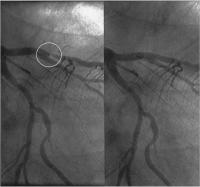

Abbildung 4: Angiogramm der linken Koronararterie: hochgradige Stenose im Ramus interventricularis anterior (Kreis). Links vor, rechts nach Stentimplantation.

Keywords: AngiographieArteria coronaria sinistraFallberichtKardiologieRamus interventricularis anteriorStenoseStent